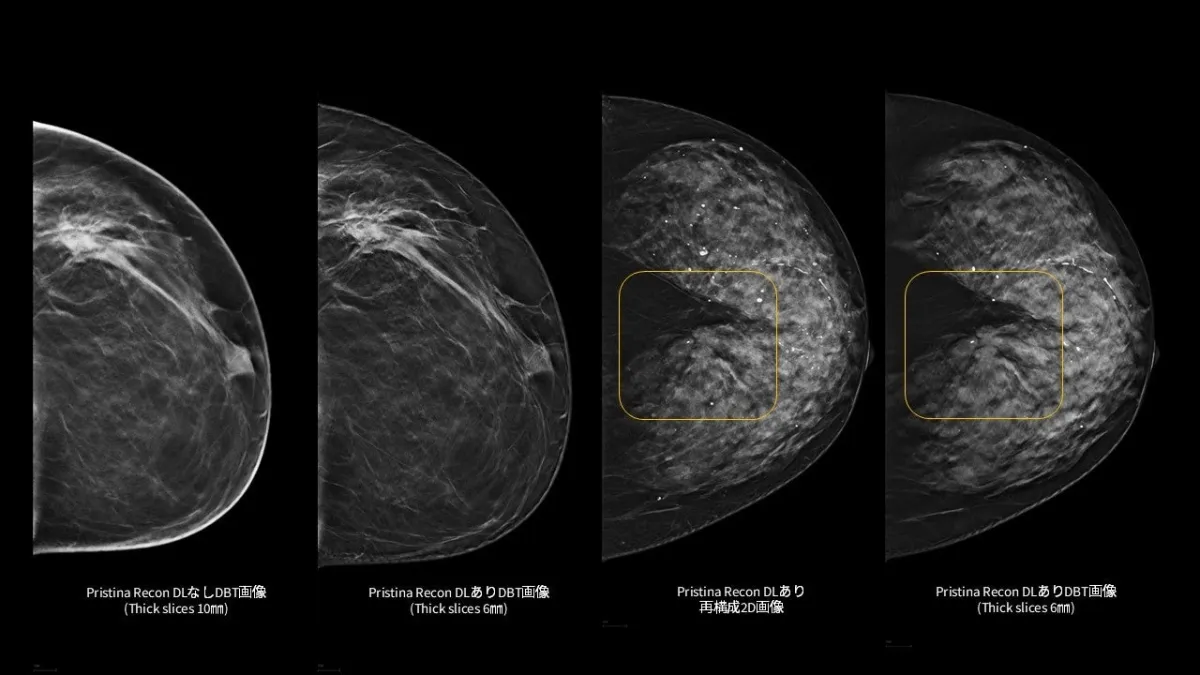

「Pristina Recon DL」は、従来のマンモグラフィの技術を一歩進めたデジタルブレストトモシンセシス (DBT/3Dマンモグラフィ) 向けの画像再構成技術です。この技術の導入により、低線量での撮影においても高品質な画像を得ることが可能になり、医療従事者による読影環境をより良好なものにすることを目指しています。

「Pristina Recon DL」は、特に視覚的ノイズやアーチファクトを低減するために設計されています。これにより、微細な構造まで明確に視認できるようになります。従来の手法に比べ、より情報が豊富で、診断に必要な視覚的インサイトを提供します。さらに、高画質画像の安定供給は医療現場における読影プロセスのスムーズさにも寄与し、医療従事者の負担を軽減します。